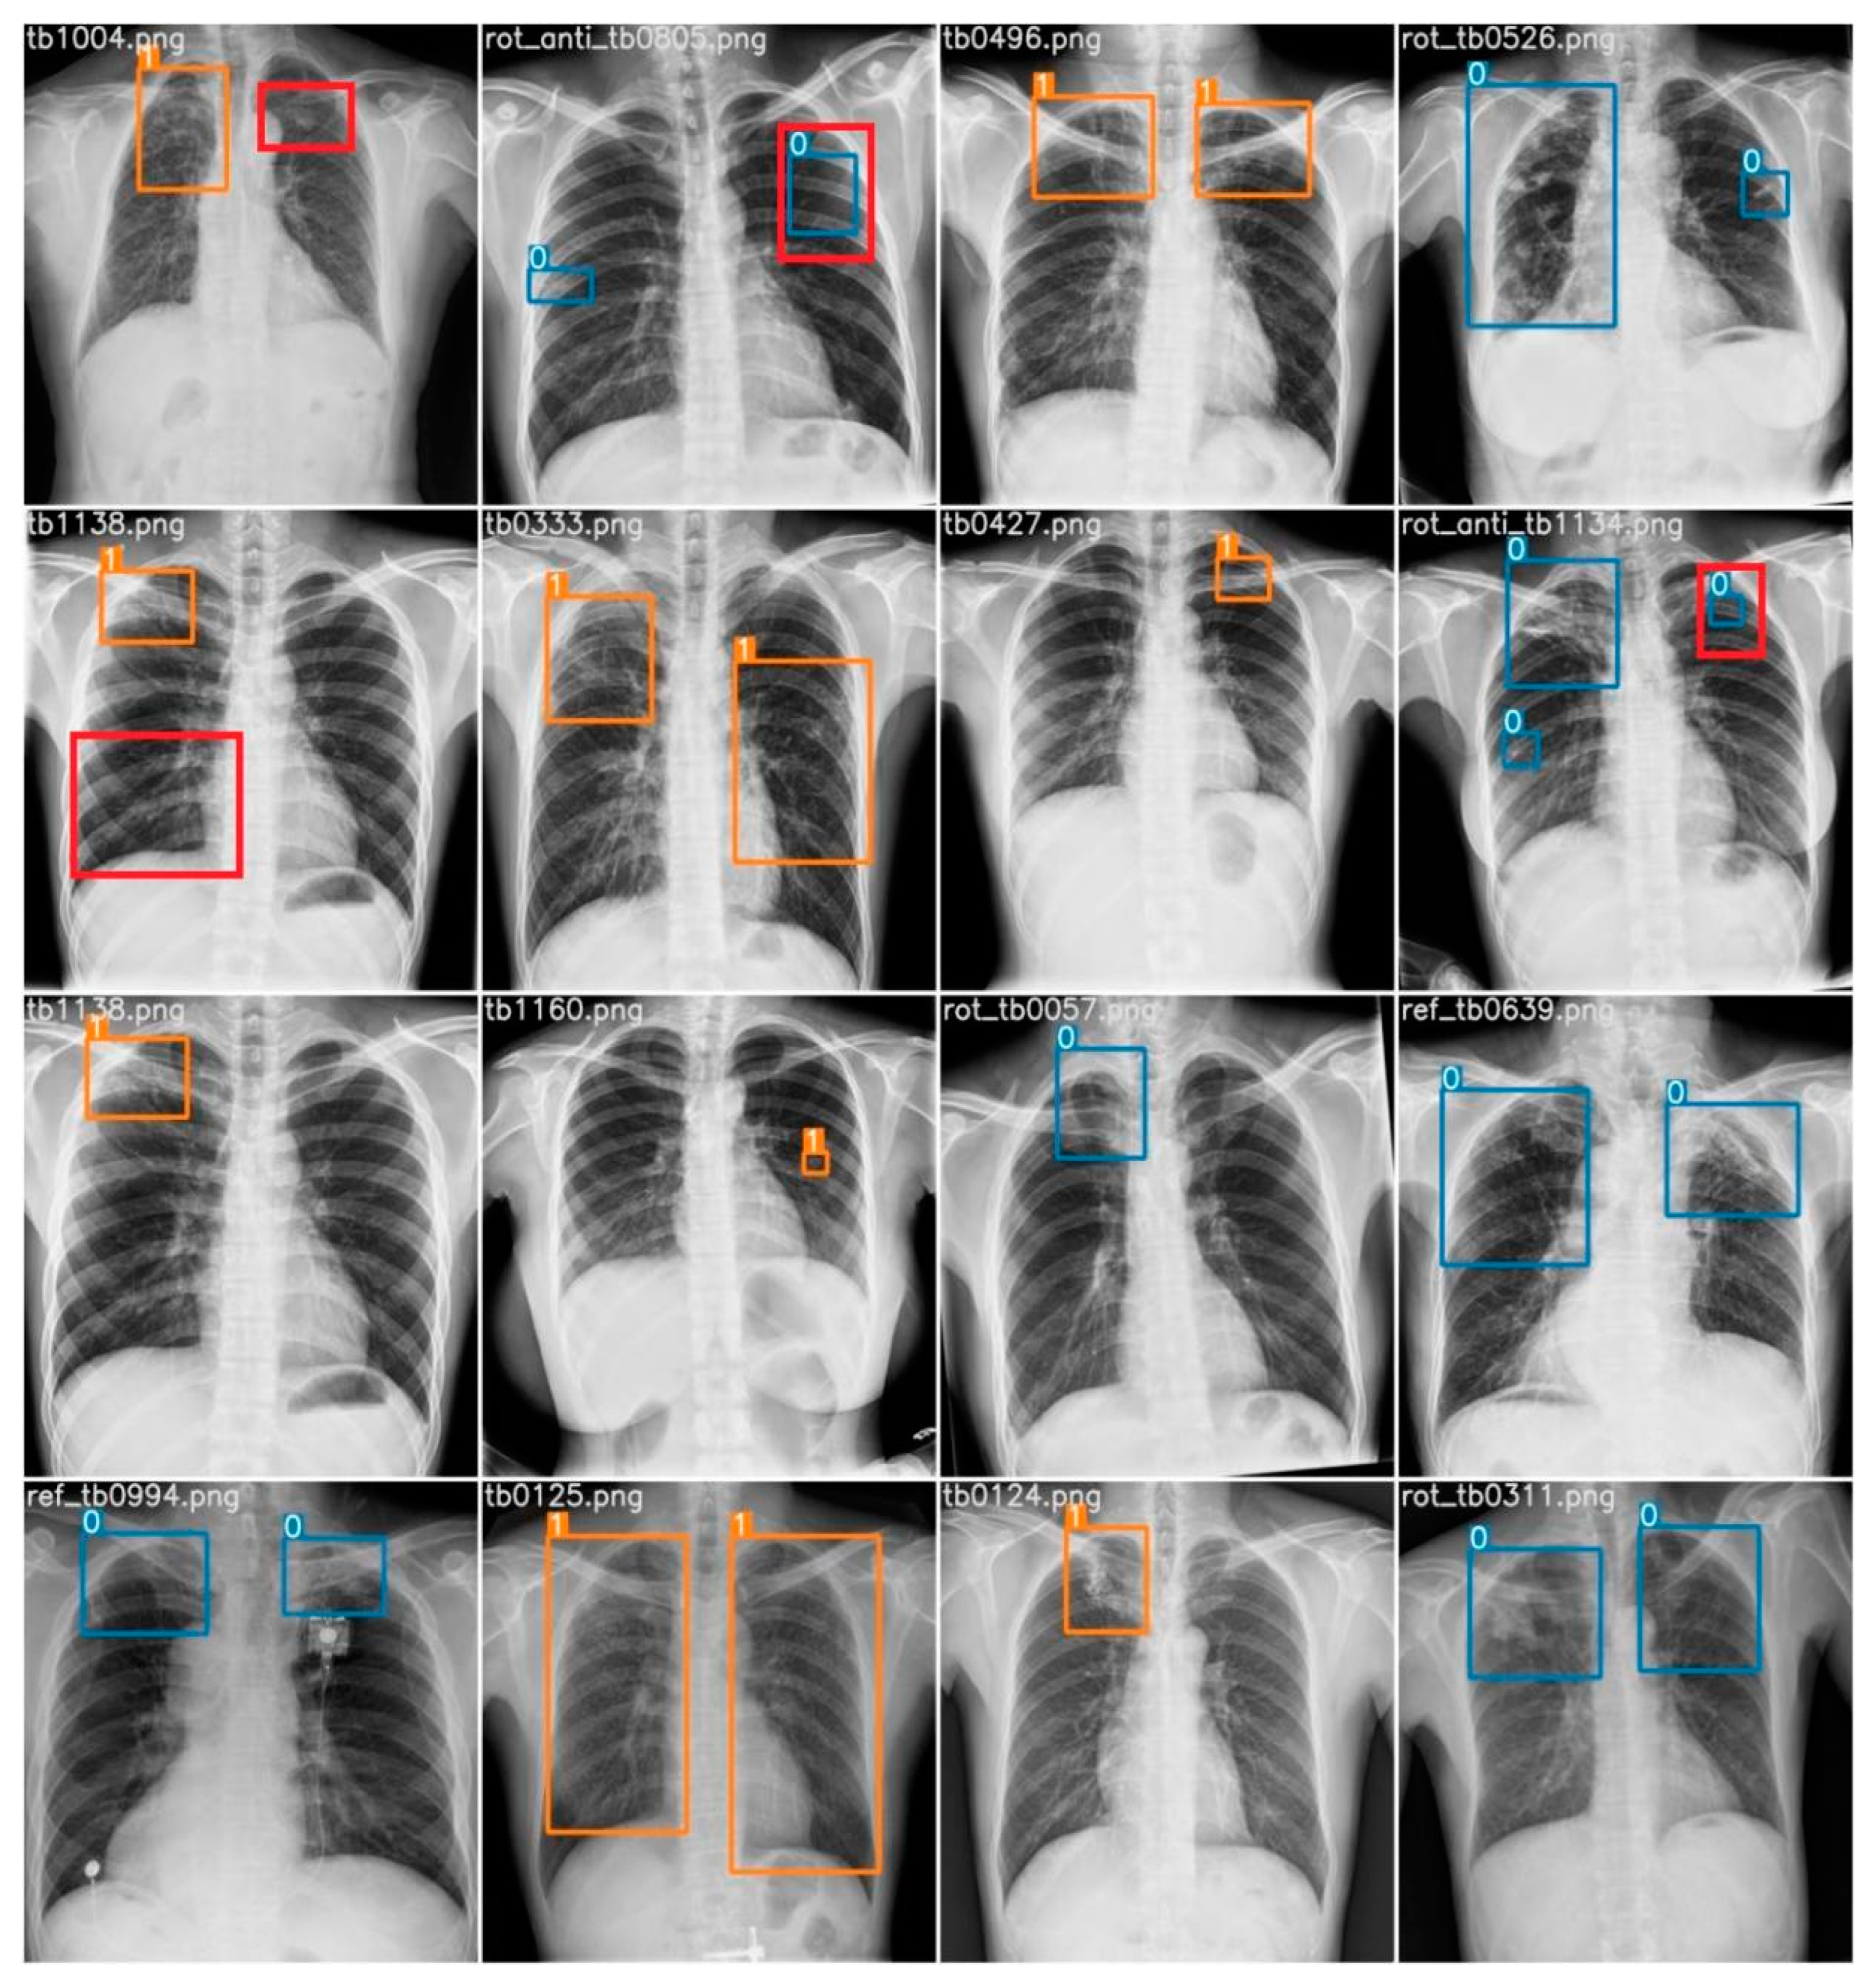

A random subset comprising 16 chest X-ray images was extracted from the dataset for analysis. Employing our computer vision model, various regions of imaging anomalies were detected within these images. To establish a benchmark, the predictions of the model were juxtaposed with interpretations provided by a radiologist, regarded as the reference standard. The radiologist identified a total of 25 abnormalities, consisting of 24 cases of airspace opacity, indicating a robust indication of TB infection, and 1 instance of cavitation. In terms of the model’s performance, there were 23 true positives, 2 false positives, and 2 false negatives. Specifically, the AI accurately identified 22 instances of airspace opacity and correctly flagged 1 case of cavitation. However, the model failed to detect two instances of airspace opacity and erroneously labeled two healthy lung regions as abnormalities. Figure 15 provides visual representations of the true positive, false positive, and false negative cases. Here, the orange box indicates an active TB infection, the blue box indicates an obsolete pulmonary TB infection, the red box indicates a false negative, and the red box outside the prediction box represents a false positive.

Figure 15. Prediction of all 16 random test samples with indication of false positives (red box outside prediction) and false negatives (red box). Here, blue box stands for obsolete cases and orange box stands for active cases.